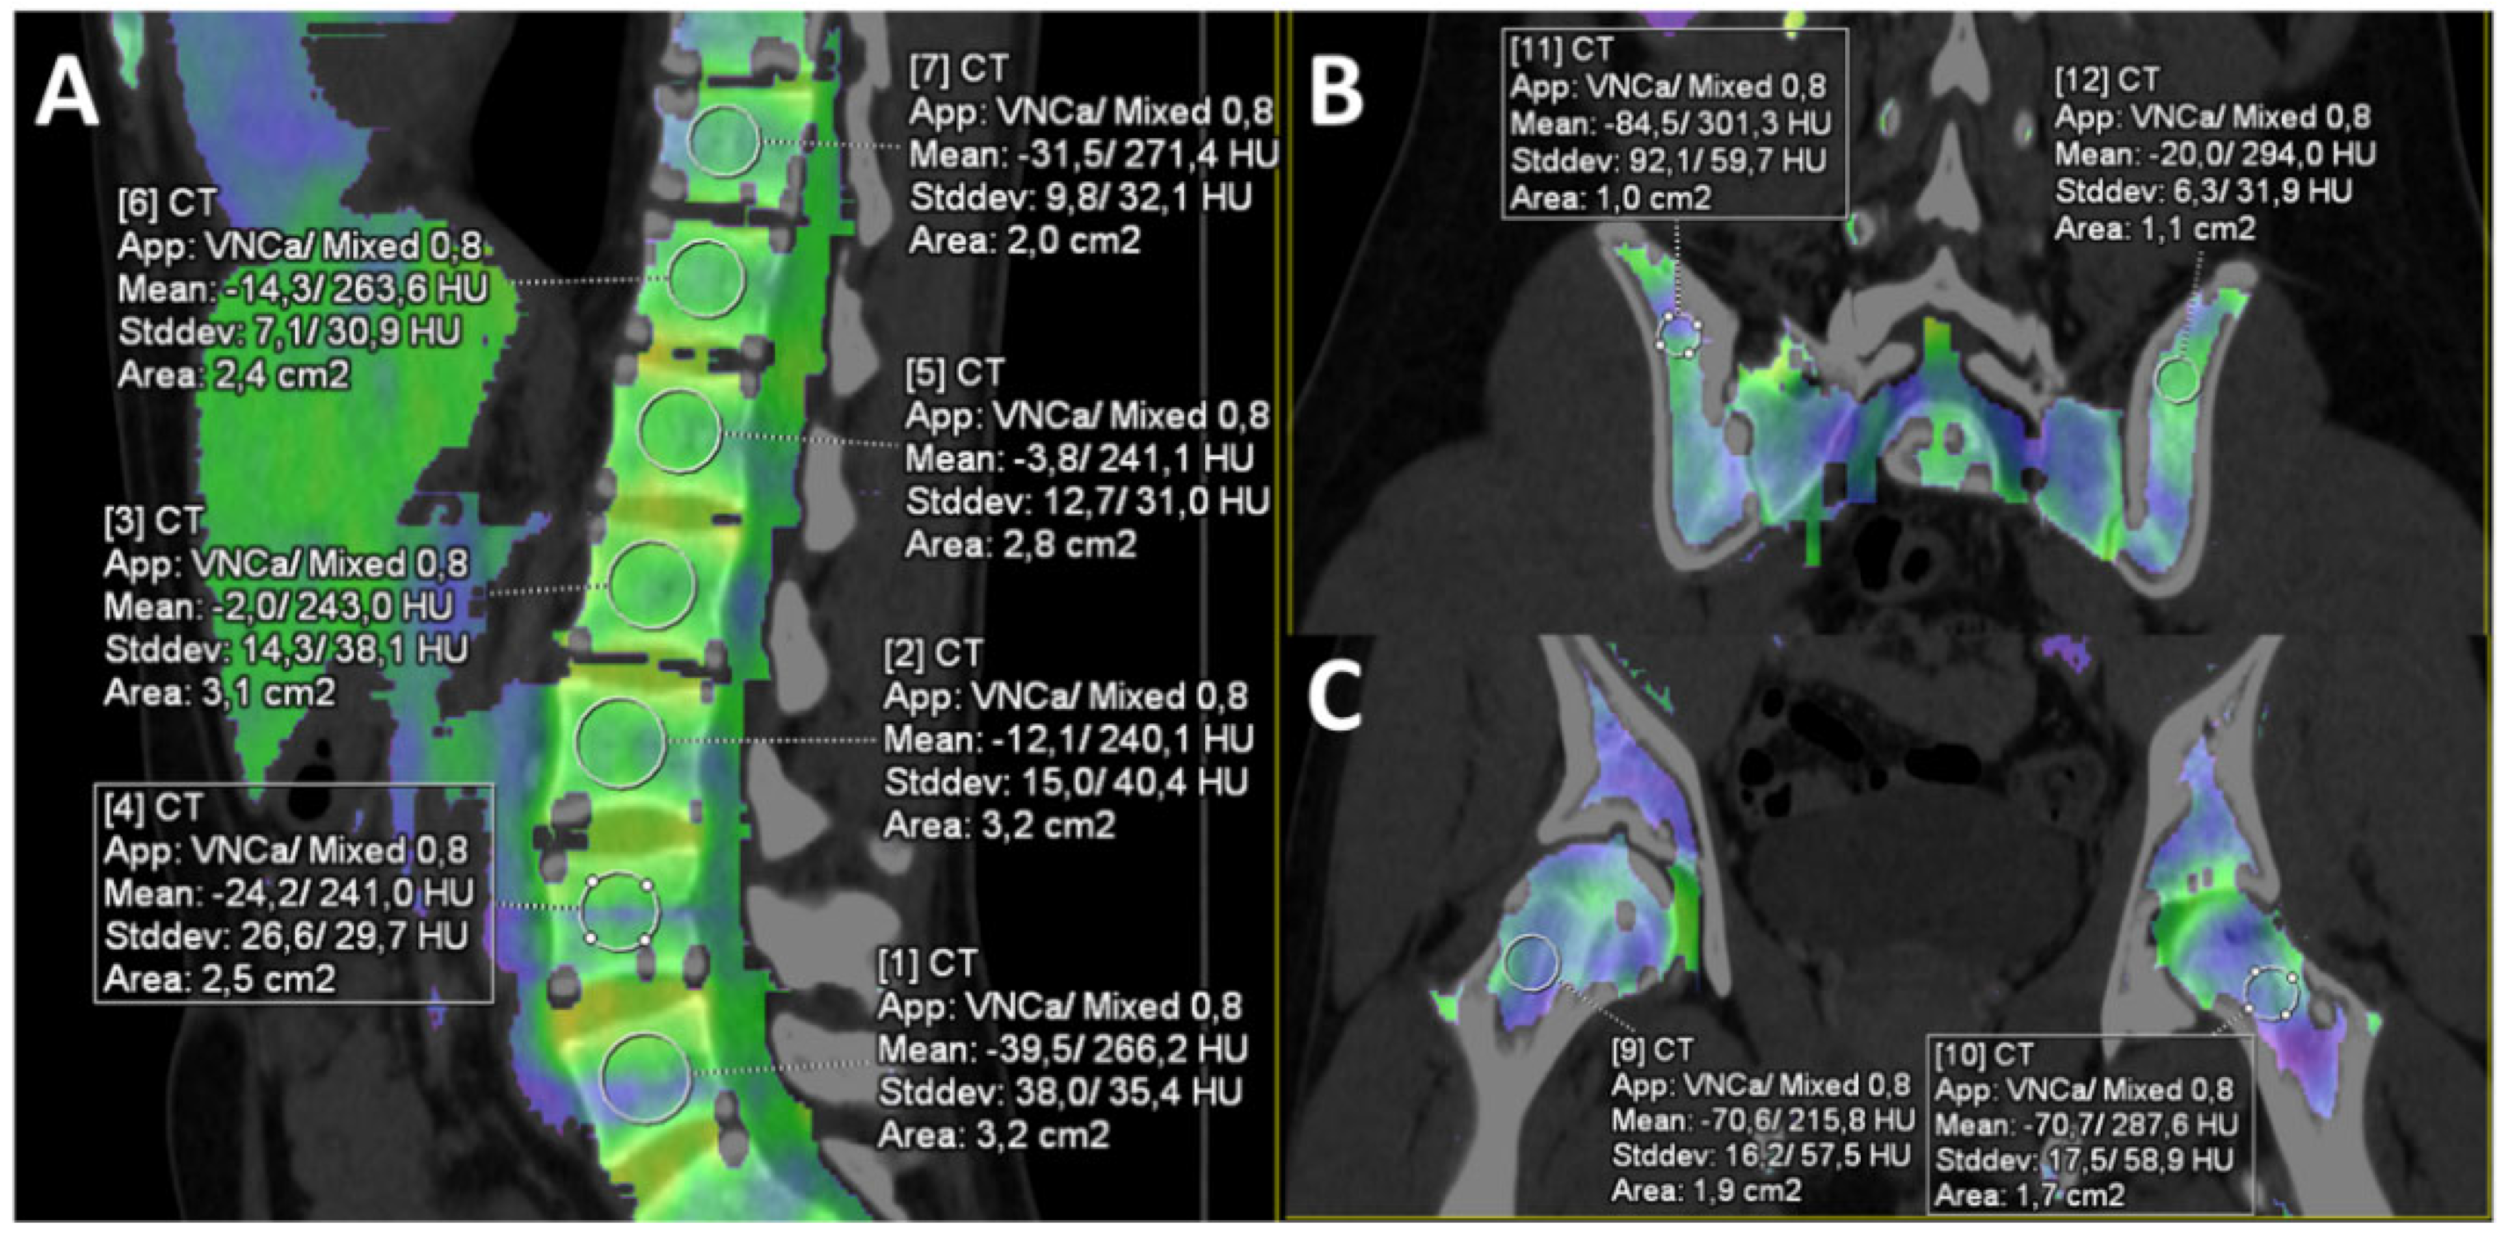

2.2. Computed Tomography Protocol and Post-Processing

2.3. Image Analysis